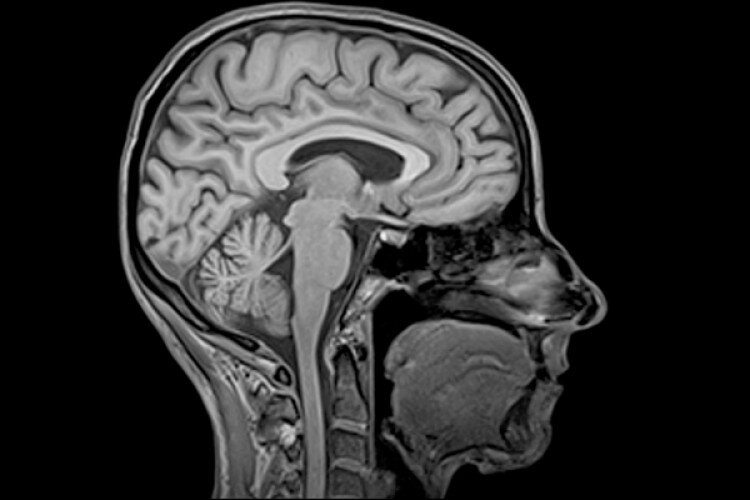

МРТ краниовертебрального перехода позволяет безошибочно диагностировать достаточно редкий порок развития - синдром Арнольда - Киари (альтернативное название - мальформации Киари, аномалия Арнольда - Киари, болезнь Киари). В медицине стандартной классификации этого заболевания нет по сегодняшний день.   Общепринятым пониманием является определение, что мальформации Арнольда -Киари - это патологические изменения в зоне задней черепной ямки и костных структур краниовертебрального перехода. В результате данной аномалии миндалины мозжечка спускаются в большое затылочное отверстие, сдавливают спинной мозг, нарушают ликвороциркуляцию, приводя к развитию сирингомиелии. Считается, что это врожденная патология, однако болезнь может манифестировать после 40 лет.

Мальформации Киари в зависимости от выраженности подразделяются на 4 типа. В большинстве ситуаций неврологам приходится иметь дело с 1 и 2 типом синдрома Арнольда - Киари.

• Мальформация Киари 1 типа - это первичное смещение или аномальное расположение мозжечка, при котором происходит эффект вклинивания миндалин ниже большого затылочного отверстия.

• Сидром Арнольда-Киари 2 типа - это дислокация цервико-медуллярного сочленения, моста, четвертого желудочка и продолговатого мозга.

• Аномалия Арнольда-Киари 3 типа - это сползание структур задней черепной ямки с проникновением мозжечковых структур в шейный канал.

• Мальформация Киари 4 типа - это аномальное недоразвитие мозжечка без проявления смещения.

Первичным шагом в обследовании больных с синдромом Арнольда - Киари является прием невролога, который дает направление на МРТ головного мозга и МРТ краниовертебрального перехода. Признаками синдрома Арнольда Киари на МРТ снимках будет:

•  заметное вклинивание миндалин мозжечка ниже большого затылочного отверстия на 5 мм и более;

• вентральная компрессия ствола мозга;

• сирингомиелия;

• наличие признаков внутричерепной гипертензии в виде нарушенной проходимости в путях циркуляции жидкости;

• нарастание ликвородинамических нарушений.